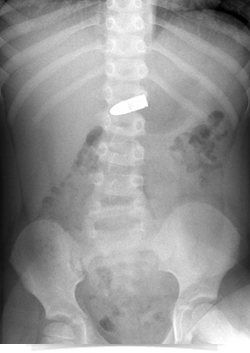

| מומחי מרכז שניידר כבר חשבו שראו הכל, אך השבוע נדהמו למצוא קליע של אקדח בקיבתו ילד בן חמש. הילד מצא את הקליע בעת טיול עם בני משפחתו לפני כשנה, השבוע שיחק איתו ובלע אותו בטעות. לאחר שדיווח להוריו שבלע את הקליע – הובהל למחלקה לרפואה דחופה (מיון) במרכז שניידר, וטופל על ידי ד"ר ערן משיח, רופא בכיר במחלקה לרפואה דחופה בשניידר. בצילום הבטן זוהה הקליע בקיבתו של הילד.  מומחי המחלקה לרפואה דחופה (מיון) ערכו התייעצויות רבות עם צוות המכון לגסטרואנטרולוגיה במרכז שניידר, עם מומחים לטוקסיקולוגיה ואפילו עם חבלן משטרה. ככלל, גופים זרים נשלפים בפעולה אנדוסקופית בחדר ניתוח, אך במקרה הזה היה חשש גדול כי מגע המתכות יוביל לתגובה כימית בגופו של הילד. לפיכך הוחלט להמתין שהקליע יצא באופן טבעי מגופו של הילד. כעבור מספר ימים, יצא הקליע מגופו של הילד.  |